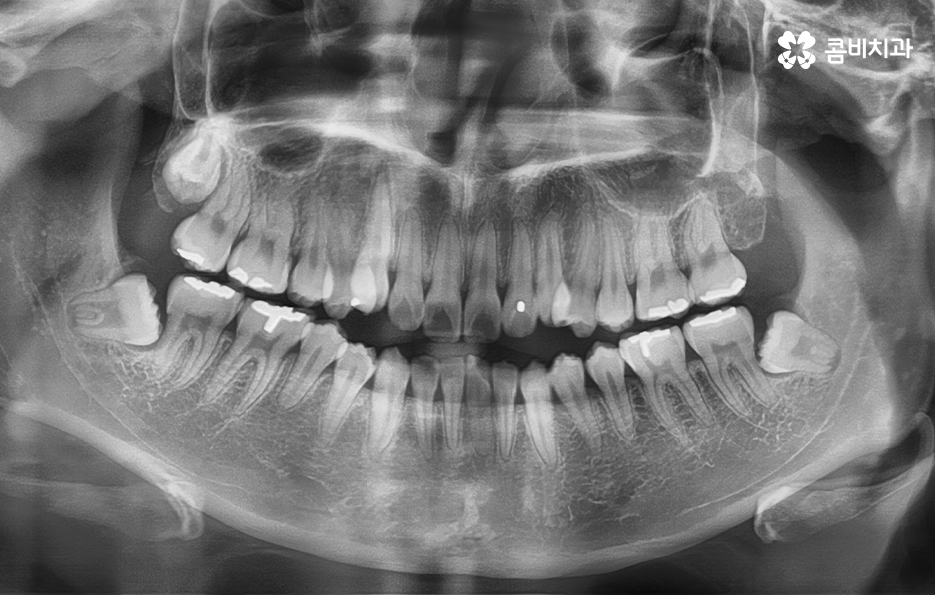

위 환자분의 경우에는 비발치로 송곳니 덧니 교정이

진행된 사례이며 전체 진료 기간은 약 1년 6개월가량이 소요되었습니다.

추가로 사랑니의 경우에도 치료 기간에 영향을 줄 수 있는데요.

교정 전에 발치를 하는 경우, 중간에 하는 경우, 끝나고 하는 경우로

나눌 수 있으며, 정밀 검사를 통해 치료 계획을 세운 뒤

순차적으로 치료를 진행하게 됩니다.